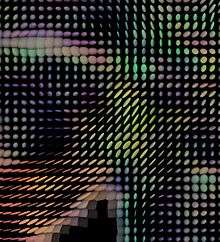

In 1990, Michael Moseley reported that water diffusion in white matter was anisotropic—the effect of diffusion on proton relaxation varied depending on the orientation of tracts relative to the orientation of the diffusion gradient applied by the imaging scanner. He also pointed out that this should best be described by a tensor.[31] Although the exact mechanism for the anisotropy has remained not completely understood, it became apparent in the early 1990s that this anisotropy effect could be exploited to map out the orientation in space of the white matter tracks in the brain, assuming that the direction of the fastest diffusion would indicate the overall orientation of the fibres, as first shown by D. Le Bihan (Douek et al.).[32] While the diffusion tensor concept was introduced in this article the authors used a simple approach in 2 dimensions (within the imaging plane) to obtain color maps of fiber orientation from the ratio between diffusion coefficients measured in the X and Y direction (Dyy/Dxx). This ratio (which is the tangent of the angle between the diffusion vector in the XY plane and the X axis) was displayed with a color scale (blue to green to red). The limitation of this "vector" approach was that Dxx and Dyy were only approximately known. Only the DTI method, which was introduced shortly after, gave access to all the components of the diffusion tensor (e.g., Dxy). In this seminal article, the authors also demonstrate that water diffusion is not really restricted, but merely hindered, even perpendicularly to the fibers, as the diffusion distance kept increasing with the diffusion time. Aaron Filler and colleagues reported in 1991 on the use of MRI for tract tracing in the brain using a contrast agent method but pointed out that Moseley's report on polarized water diffusion along nerves would affect the development of tract tracing.[33] A few months after submitting that report, in 1991, the first successful use of diffusion anisotropy data to carry out the tracing of neural tracts curving through the brain without contrast agents was accomplished.[29][34][35] Filler and colleagues identified both vector and tensor based methods in the patents in July 1992,[35] before any other group, but the data for these initial images was obtained using the following sets of vector formulas that provide Euler angles and magnitude for the principal axis of diffusion in a voxel, accurately modeling the axonal directions that cause the restrictions to the direction of diffusion:

The first color maps of white matter fiber orientation using diffusion MRI (Douek et al. 1991) [1]

The first vector calculated image using diffusion anisotropy to show neural tracts curving through the brain in Macaca fascicularis (Filler et al. 1992)[2]